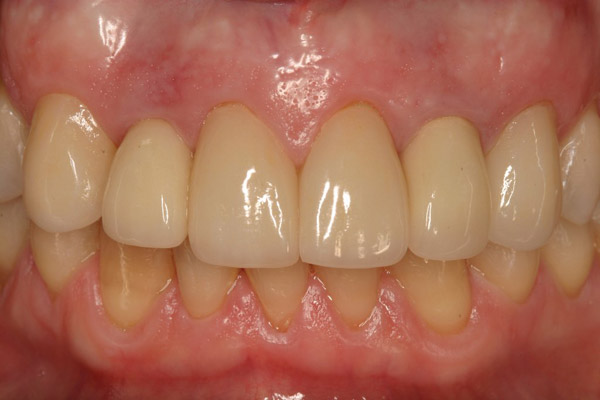

Figure 18  Periapical radiographs of the final implants show good bone levels and interproximal spacing between the implants and adjacent teeth.

Figure 18

Figure 19  The post-implantation and post-restoration view shows esthetically pleasing, symmetric crowns and mucosal contours, with the Nos. 7 and 10 implant prostheses blending in imperceptibly with the natural dentition. Restoration courtesy of Dr. Jeffrey Warren.

Figure 19